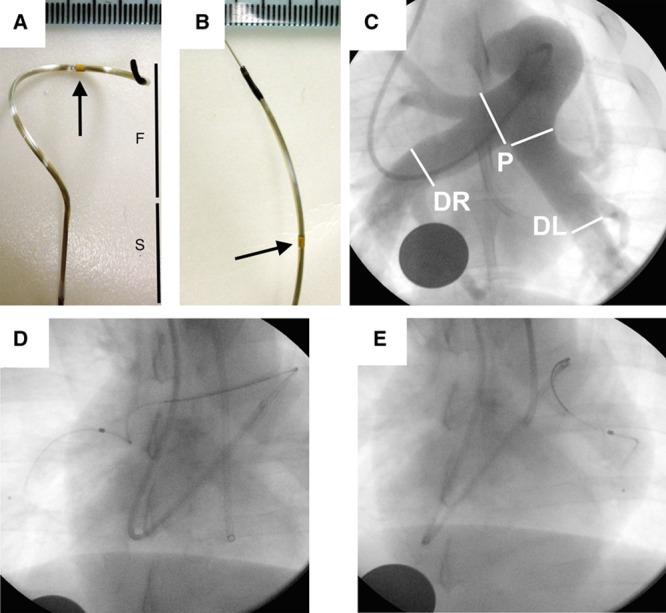

Histological evaluation identified a circumferential distribution of nerves around the proximal pulmonary arteries. Nerves were smaller in diameter, greater in number, and located in closer proximity to the luminal aspect of the pulmonary arterial wall beyond the pulmonary artery bifurcation. To determine the effect of pulmonary arterial denervation acute pulmonary hypertension was induced in 8 pigs by intravenous infusion of thromboxane A2 analogue. Animals were assigned to either pulmonary artery denervation, using a prototype radiofrequency catheter and generator, or a sham procedure. Pulmonary artery denervation resulted in reduced mean pulmonary artery pressure and pulmonary vascular resistance and increased cardiac output. Ablation lesions on the luminal surface of the pulmonary artery were accompanied by histological and biochemical alteration in adventitial nerves and correlated with improved hemodynamic parameters.